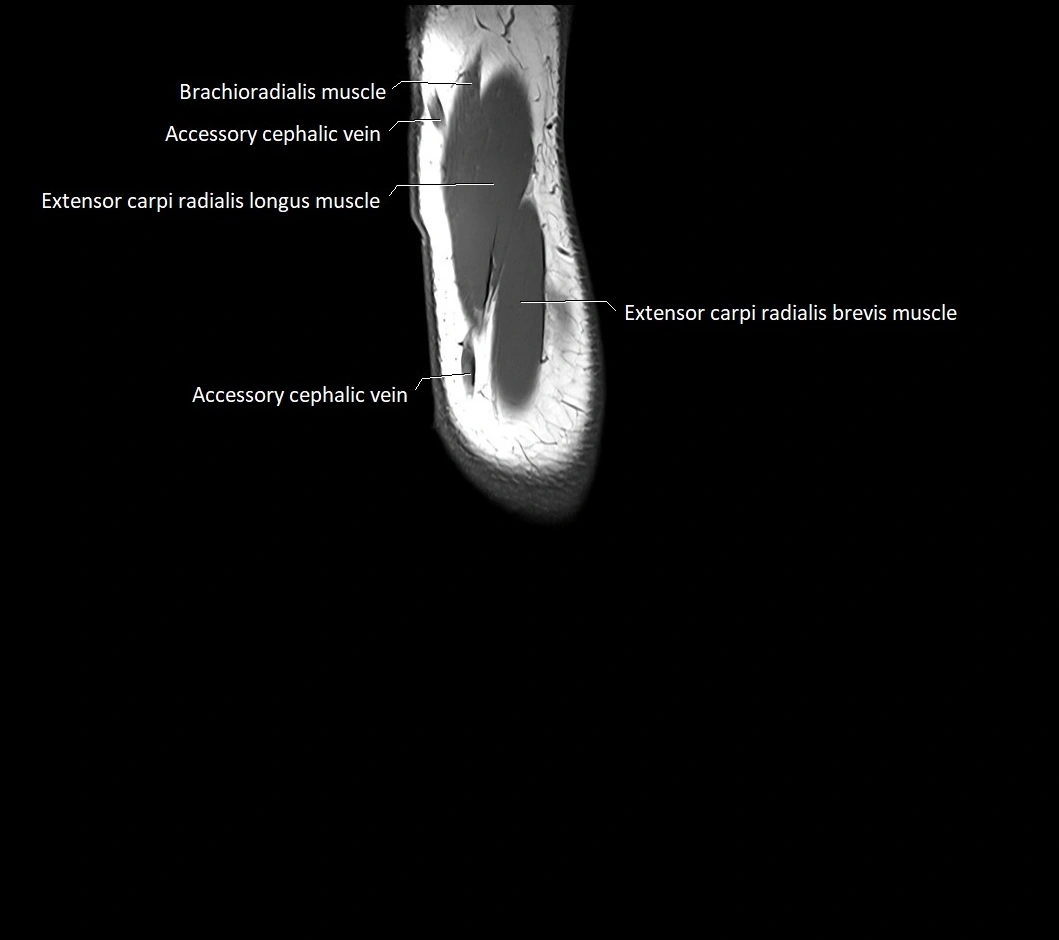

MRI images

image